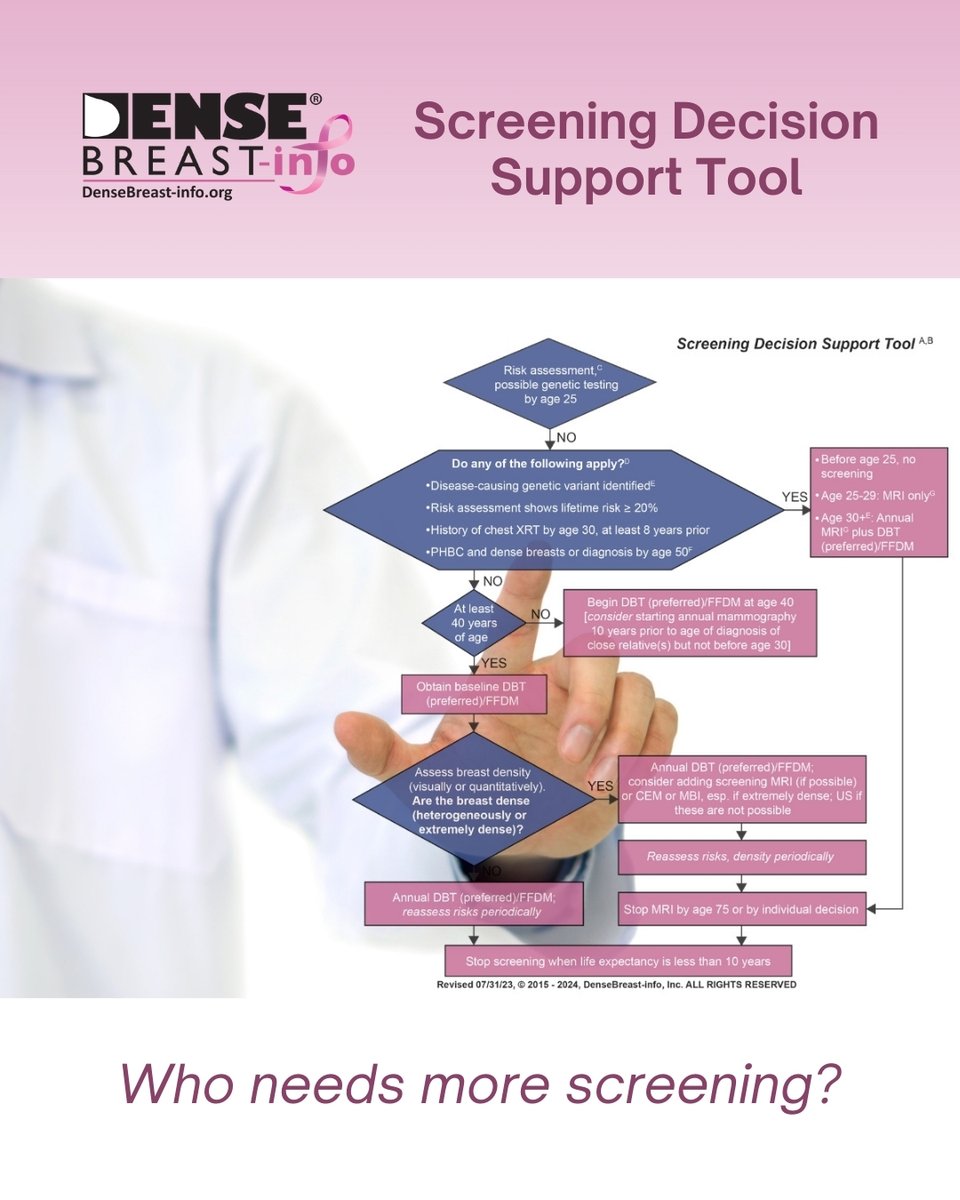

When is a mammogram not enough? Risk assessment is recommended for all women at age 25, to potentially start screening MRI at that time if at high risk. DenseBreast-Info.org breast density should be considered, along with family history and prior biopsies. futureofpersonalhealth.com/breast-health/…